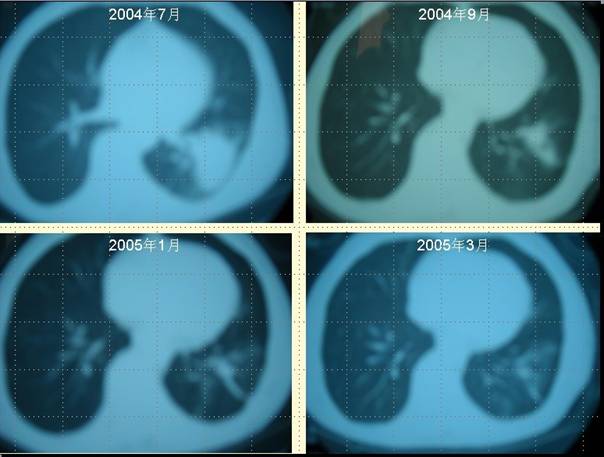

案例二 柴XX的病理圖片

肺癌病人柴XX采用“董氏治癌法”治療前后 CT對照變化